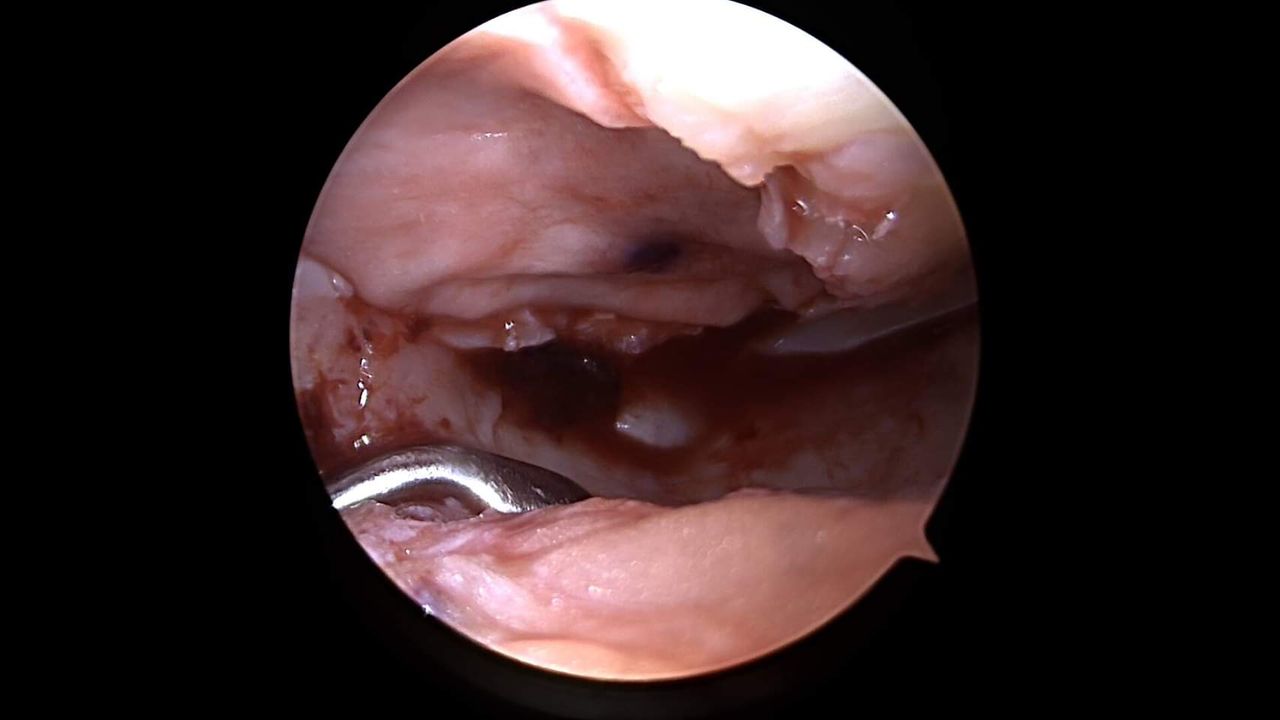

Dal 2005 Responsabile di Unita'​ Operativa di Endoscopia articolare presso la Casa di Cura Igea di Partinico ( Palermo ), con particolare dedizione alla chirurgia artroscopica di ginocchio.

Casistica personale : circa 10000 interventi di chirurgia artroscopica di ginocchio (trattamento di tutta la patologia meniscale, delle lesioni legamentose riguardanti il legamento crociato anteriore - posteriore e collaterali, della patologia sinoviale e delle lesioni cartilaginee con trapianti osteocondrali e tecniche utilizzanti cellule staminali in associazione con membrane semisintetiche tridimensionali di estere benzilico di acido ialuronico o con membrane biologiche di collagene porcino). Correzione delle deviazioni assiali degli arti con osteotomie correttive; correzione del malallineamento femoro rotuleo in artroscopia e artrotomia, chirurgia protesica.